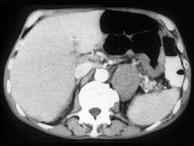

问题 男,57岁,腹部隐痛不适伴低热2月余,腋下可触及数个肿大的淋巴结,请结合图像,作出诊断 ( )

选项 A、左侧肾上腺腺瘤 B、左侧肾上腺转移瘤 C、左侧恶性嗜铬细胞瘤侵及胃脾 D、左侧肾上腺淋巴瘤且胃脾受累 E、左侧肾上腺癌并胃脾转移

答案 D